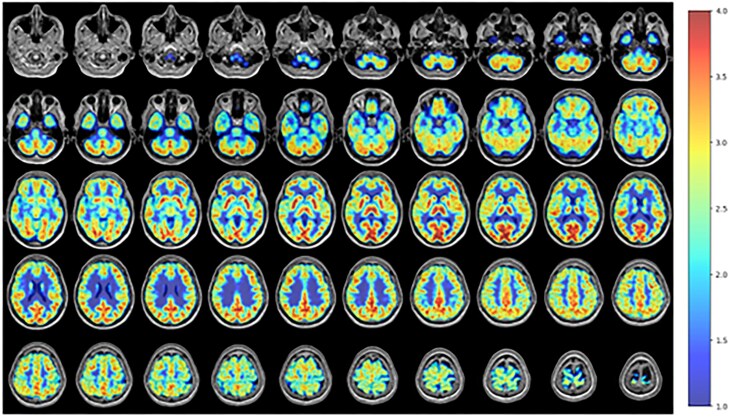

Case presentation: Our participant is a 58 year-old male with a past medical history notable for alcohol use disorder and BD (unspecified type) who underwent PET imaging with the mitochondrial complex I PET ligand 18F-BCPP-EF. The resulting images demonstrated significant overlap between areas of dysfunction identified with the 18F-BCPP-EF PET ligand and prior functional magnetic resonance imaging (MRI) techniques in the setting of BD. That overlap was seen in both affective and cognitive circuits, with mitochondrial dysfunction in the fronto-limbic, ventral affective, and dorsal cognitive circuits showing particularly significant differences.

Abstract Image